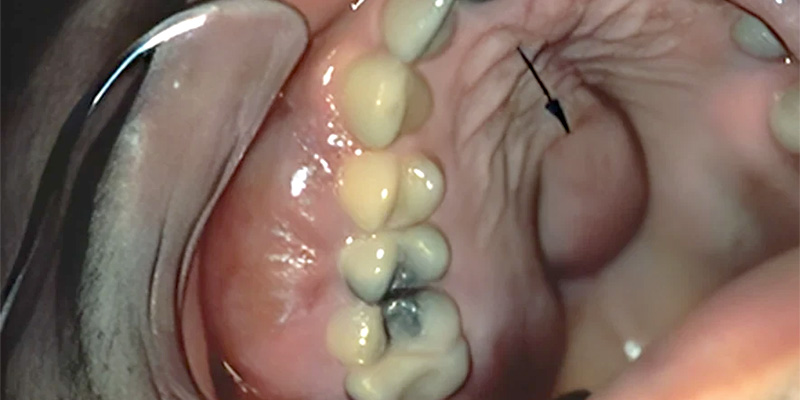

Le tabagisme chronique associé à l’alcoolisme sont les facteurs étiologiques essentiels, touchant en général une population socio-économiquement défavorisée. Cette double intoxication alcool-tabac s’accompagne souvent d’un état bucco-dentaire médiocre et négligé.

• L’étiologie étant à 80% une intoxication alcool-tabac dans un contexte bucco-dentaire médiocre, la population à risque est simple à cibler.